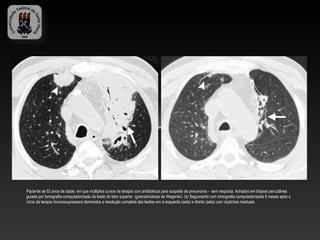

Paciente de 53 anos de idade, em que múltiplos cursos de terapia com antibióticos para suspeita de pneumonia - sem resposta. Achados em biópsia percutânea

guiada por tomografia computadorizada da lesão do lobo superior (granulomatose de Wegener). (b) Seguimento com tomografia computadorizada 9 meses após o

início da terapia imunossupressora demonstra a resolução completa das lesões em a esquerda (seta) e direito (seta) com cicatrizes residuais.